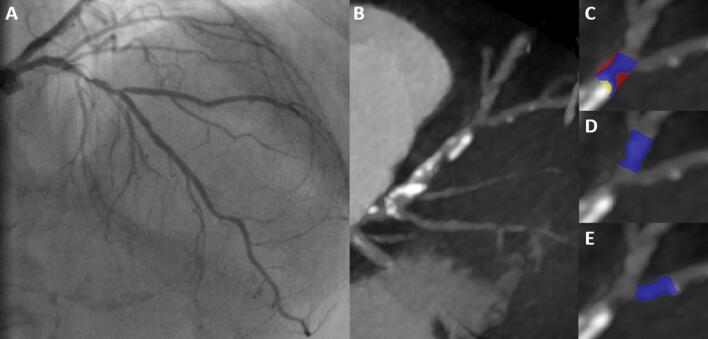

We included 340 patients with 377 bifurcation lesions in the post hoc analysis of the CT-PRECISION registry. Each bifurcation was divided into three segments: the proximal main vessel (MV), the distal MV, and the SB. Segments with evidence of coronary plaque were analyzed using semi-automated software allowing for quantitative analysis of coronary plaque morphology and stenosis. Coronary plaque measurements included calcified and noncalcified plaque volumes, and corresponding burdens (respective plaque volumes × 100%/vessel volume), remodeling index, and stenosis.

SB occlusion occurred in 28 of 377 bifurcation lesions (7.5%). The presence of visually identified plaque in the SB segment, but not in the proximal and distal MV segments, was the only qualitative parameter that predicted SB occlusion with an area under the curve (AUC) of 0.792. Among quantitative plaque parameters calculated for the SB segment, the addition of noncalcified plaque burden (AUC 0.840, p = 0.003) and low-density plaque burden (AUC 0.836, p = 0.012) yielded significant improvements in predicting SB occlusion. Using receiver operating characteristic curve analysis, optimal cut-offs for noncalcified plaque burden and low-density plaque burden were > 33.6% (86% sensitivity and 78% specificity) and > 0.9% (89% sensitivity and 73% specificity), respectively.

CTA-derived noncalcified plaque burden, when added to the visually identified SB plaque, significantly improves the prediction of SB occlusion in coronary bifurcation intervention.